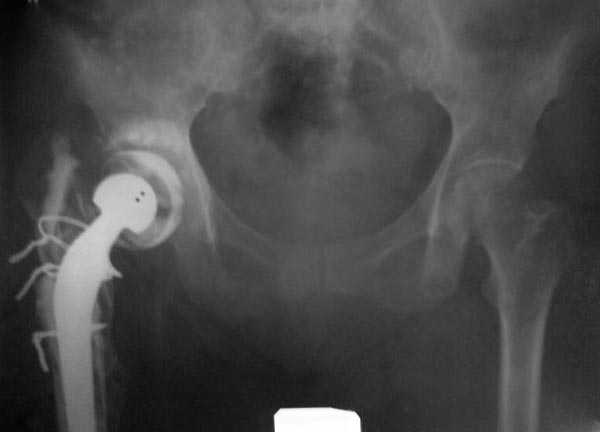

Как-то показывал случай после осложненного тотального эндопротеза,

сперва из-за отсутствия экономических возможности, а затем привыкшая

к своей участи вот уже более 8 лет ходит на временном

"протезе-спейсере".

Имя     : #4 tu ap pelvis.jpg

Тип     : image/jpeg

Размер  : 20715 байтов

Описание: отсутствует

Url     : http://weborto.net:8080/pipermail/ortho/attachments/20080325/18bca692/attachment-0010.jpg